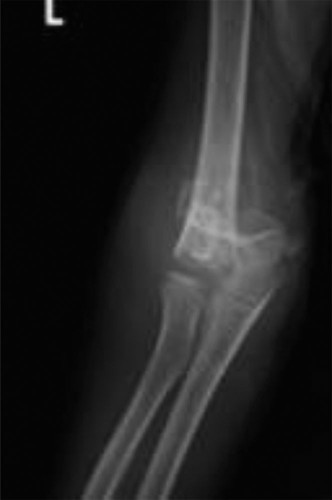

CASE 1 An 8-year-old girl is brought to the ER by her mother after she fell from the monkey bars during reces…